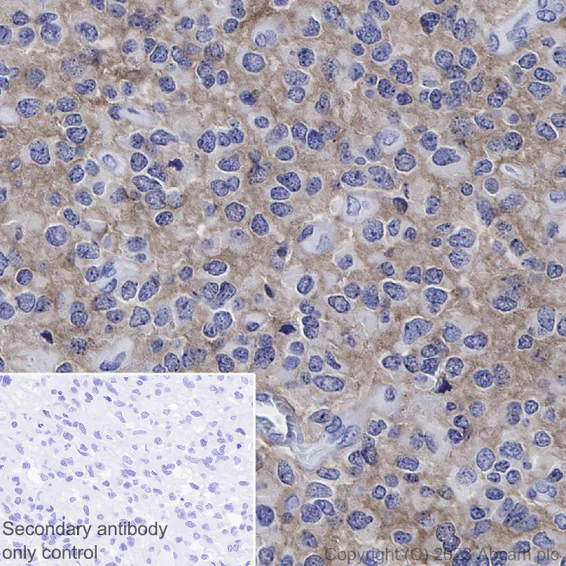

Immunohistochemical analysis of paraffin-embedded Human diffuse large B-cell lymphoma labelling CD10 with ab255609 at 1/1000 dilution, followed by a Goat Anti-Rabbit IgG H&L (HRP polymer) ready to use (ab214880). Positive staining on human diffuse large B-cell lymphoma is observed. Counter stained with hematoxylin. Secondary antibody only control : Used PBS instead of primary antibody, secondary antibody is a Goat Anti-Rabbit IgG H&L (HRP polymer) ready to use. Heat mediated antigen retrieval using ab93684 (Tris/EDTA buffer, pH 9.0).